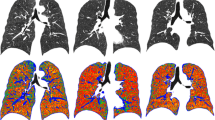

We analysed 45 subjects from a lung cancer screening trial, examined by CT twice within 3 months. Inspiratory and expiratory low-dose CT was obtained using breath hold instructions. CT air trapping was defined as the percentage of voxels in expiratory CT with an attenuation below −856 HU (EXP−856) and the expiratory to inspiratory ratio of mean lung density (E/I-ratioMLD). Variation was determined using limits of agreement, defined as 1.96 times the standard deviation of the mean difference. The effect of both lung volume correction and breath hold reproducibility was determined.

The lungs were automatically segmented using dedicated software [11], and a noise reduction filter was applied to decrease the influence of noise on the quantitative measurements [12]. Briefly, the lungs were segmented from the chest wall, mediastinum, diaphragm and airways in both inspiratory and expiratory CT images. Total volume and attenuation of all voxels included in the lung segmentation was calculated and a density histogram created, from which the quantitative CT air trapping measures were extracted. Lung segmentation was visually checked in all CT pairs of each participant. The extent of CT air trapping was defined as the percentage of voxels in expiratory CT with an attenuation below −856 HU (EXP−856) [5] and as the expiratory to inspiratory ratio of mean lung density (E/I-ratioMLD) [13], which are both currently available techniques to quantify air trapping in COPD on CT. Quantitative results are presented as percentage.

Variability in quantitative CT assessment of air trapping

Inspiratory and expiratory volumes generally showed good repeatability; the median (interquartile range) absolute differences in total lung volume were −145 mL (−303 to 149) for inspiratory volume, −116 mL (−424 to 157) for expiratory volume, and 26 mL (−385 to 393) for exhaled volume. The association between the two acquisitions is illustrated in Fig. 2.

At baseline, CT air trapping measures ranged from 0.5 to 59.1 % for EXP−856, and from 64.5 to 95.1 % for E/I-ratioMLD. At repeat CT examination, this was 0.9 to 67.5 % for EXP−856, and 70.7 to 96.5 % for E/I-ratioMLD. CT air trapping between the two acquisitions showed a concordance correlation coefficient of 0.886 (EXP−856) and 0.741 (E/I-ratioMLD). The difference in CT air trapping between the two acquisitions ranged from −13.3 to 19.6 % for EXP−856, and from −13.9 to 9.9 % for E/I-ratioMLD.